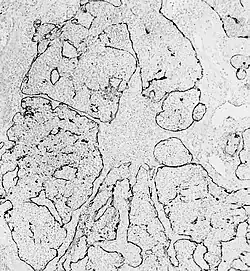

Esthesioneuroblastoma is of neurocrest origin, arising from olfactory sensory cells in the olfactory epithelium.[1] The olfactory epithelium consists of olfactory sensory cells, sustentacular cells and basal cells.[1] Esthesioneuroblastoma consists of lobular sheets with neurofibrilar fibers and rosettes.[4] Hyam's classifications are an important way of determining prognosis.[10]